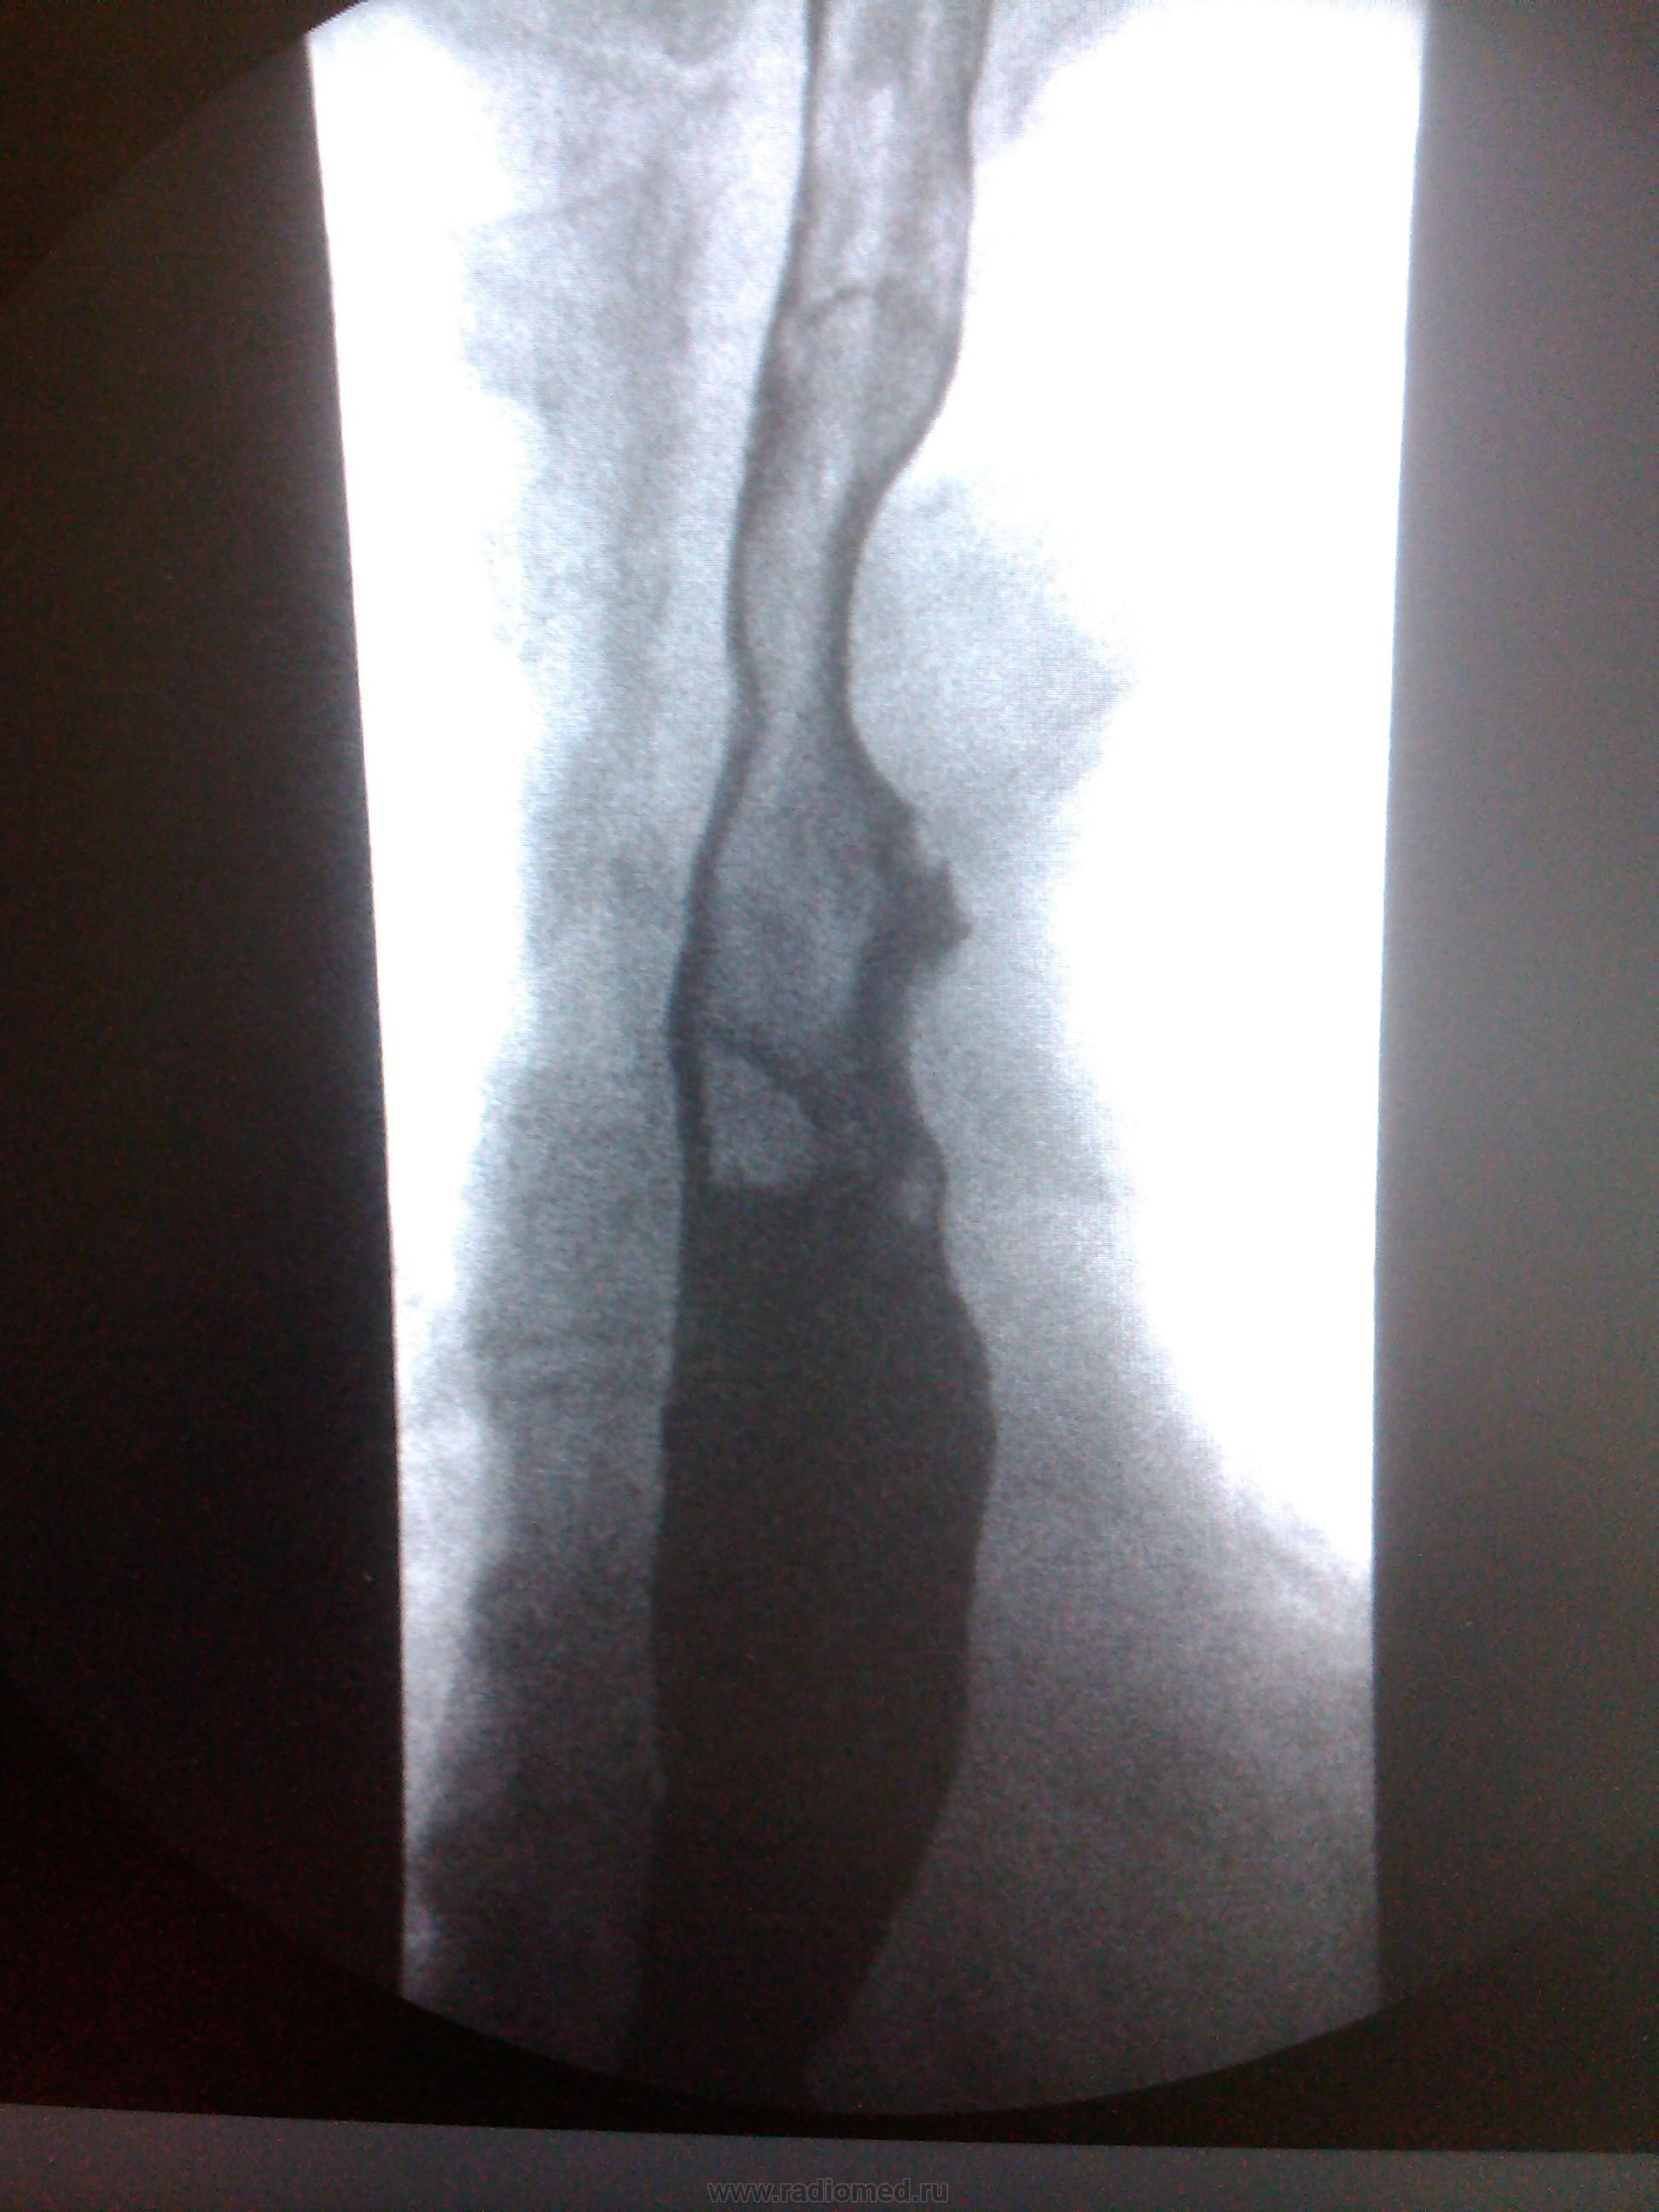

Пациентка, 74 года. Операция по поводу дивертикула пищевода лет 25 назад. Нужны мнения!

Ахалазия кардии, скользящая грыжа пищеводного отверстия диафрагмы, мелкий дивертикул с/3 пищевода - это мнение.

Тракционный дивертикул пищевода. ГПОД. Эзофагоспазм. За ахалазию сомнительно. А вот почему пищевод такой широкий - стоит задуматься.

Может быть он гипотоничный + третичные сокращения вот и выглядит широким, возможно там и эзофагит.

Я такие широкие пищеводы вижу регулярно при склеродермии, например. И клиницисты как бы должны знать о ее существовании, например же. Наше дело - констатировать факты, а их интерпритацию стоит все же оставить другим докторам.

"Нужны мнения!" Мнение: плохо оперировали тогда или: не причину, а следствие. Дивертикул есть и лит есть. ИМХО. А где причина - коллеги по поводу дистального отдела отд. пищевода  уже писали. Теоретически - проблема с 12п. кишкой( по Витебскому)